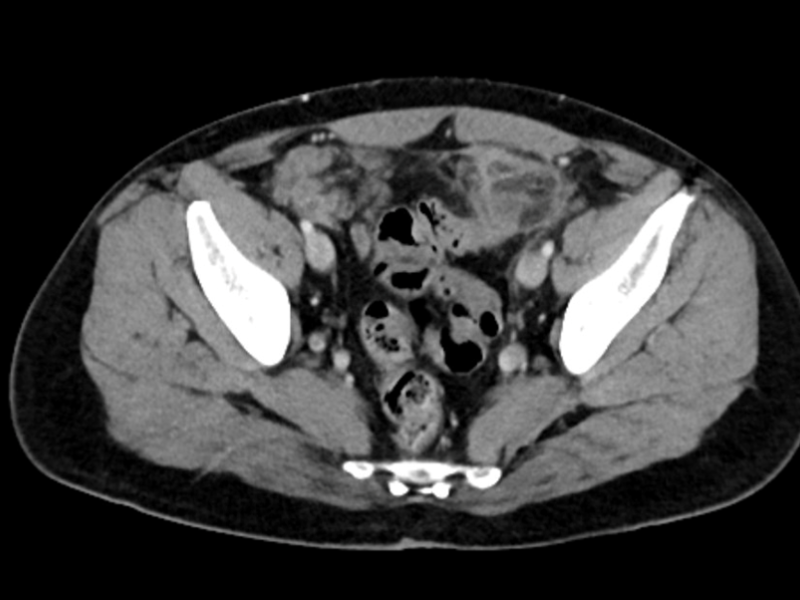

A 40 year old female with a history of kidney stones with a